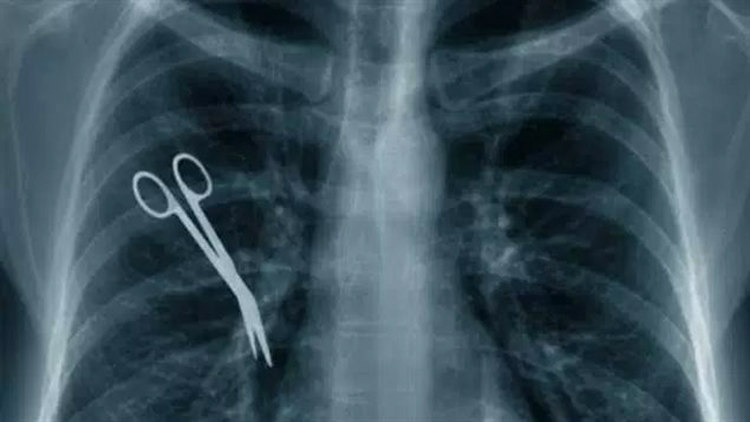

4 Medical mistakes kill over 250,000 Americans each year. If they were a disease, they would be the 3rd leading cause of death in the US.

Surgical-Medical Mistakes

Image Source: rcinet

According to a study by surgeon and John Hopkins University professor, Martin Makary, medical mistakes are the third leading cause of deaths in the U.S., the first being heart disease and the second cancer. According to an estimate by the National Academy of Science’s Institute of Medicine, 98,000 deaths are attributed each year to medical errors. In 2010, 180,000 Medicare patient deaths were reported by the Inspector General of the Department of Health and Human Services. In 2013 a NASA toxicologist whose son died of what he believes to be medical error estimated the deaths to be between 210,000 and 440,000 a year.(source)